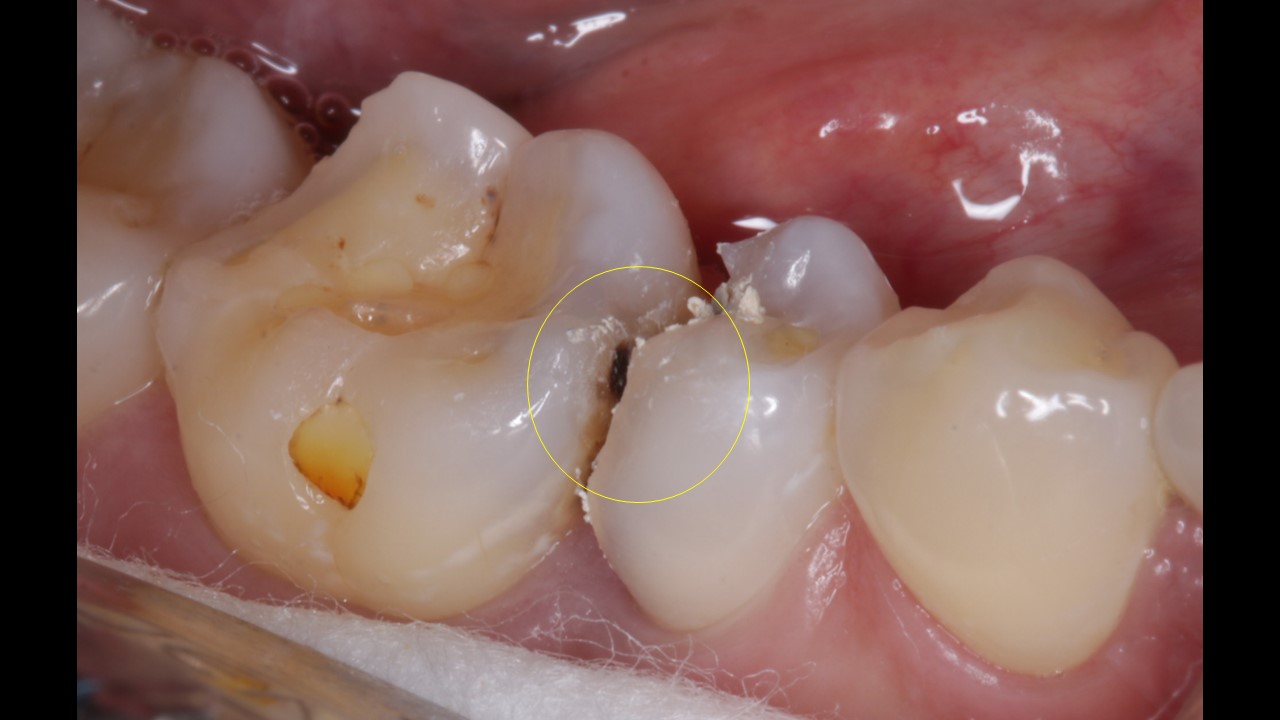

Patient presented with pain and discomfort in the lower right second premolar. Pain was of radiating type accompanied with food lodgement. On examination, the lower right 2nd premoalr was decayed with a portion of the distal surface lost due to the process of deacy. Examination alos revealed decay of the molar on the mesial side. Typical presentation that accompanies food lodgement and decay.

Root canal therapy (RCT)in lower right 2nd premolar and lower left 1st molar.

Post (fiber) and core , Emax onlay